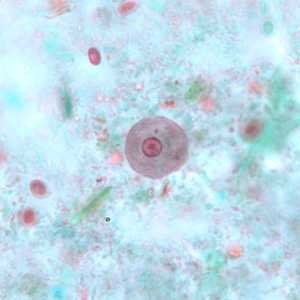

I. buetschlii cysts stained with trichrome.

Figure A: Cyst of I. buetschlii stained with trichrome. In this specimen, both the nucleus and large glycogen vacuole are visible.

Figure B: Cyst of I. buetschlii stained with trichrome. In this specimen, both the nucleus and large glycogen vacuole are visible.

Figure C: Cyst of I. buetschlii stained with trichrome. In this specimen, both the nucleus and large glycogen vacuole are visible (arrow).

Figure D: Cyst of I. buetschlii stained with trichrome. In this specimen, both the nucleus and large glycogen vacuole are visible.